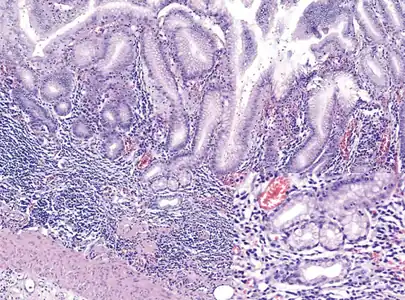

- Histopathology of antral mucosa with atrophy. H&E 10x. Antral gastric mucosa with accentuated atrophy because replacement by extensive intestinal metaplasia.